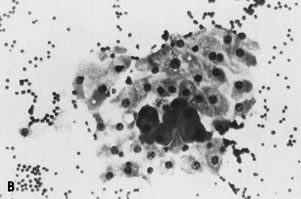

Benign, reactive conditions generally yield cellular specimens composed of a dyscohesive (i.e., single cell) population of lymphoid cells. Lymphocytes in a number of different states of activation are present, including small mature lymphocytes, large activated cells, immunoblasts, and plasma cells, resulting in the classic polymorphous population of lymphocytes indicative of a reactive condition (Fig. 8A).59 Histiocytes may also be present, often with ingested intracytoplasmic cellular debris (“tingible body” macrophages) and also suggest a reactive process. In contrast, aspirates of lymphoma yield a dyscohesive population of lymphoid cells in an abnormal distribution, with one subpopulation in dominance, resulting in the classic monotonous population typical of malignant lymphoma (Fig. 8B). Such a monotonous population of small, intermediate, or large lymphoid cells without the accompanying cell types just described is highly suggestive of lymphoma.59 Material from an FNA may be submitted for immunophenotyping by flow cytometry, in the hopes of objectively showing a monotypic cell population, consistent with malignancy. Although surgical biopsy may be required for further subclassification of some types of lymphoma, FNA with flow cytometry may be used for diagnosing and subclassifying cases of primary and recurrent non-Hodgkin lymphoma.60–63 Such an approach is particularly appropriate for deep-seated masses in which open biopsy is technically difficult and perhaps even contraindicated in debilitated patients.

Fig. 8. ( A) Fine-needle aspiration (FNA) of reactive lymph node shows polymorphous population of small, mature lymphocytes and larger activated lymphoid cells, consistent with lymphoid hyperplasia (stain, Diff-Quik); compare with ( B) FNA of malignant lymphoma displaying monotonous population of large lymphoid cells, consistent with large cell lymphoma (stain, Diff-Quik).